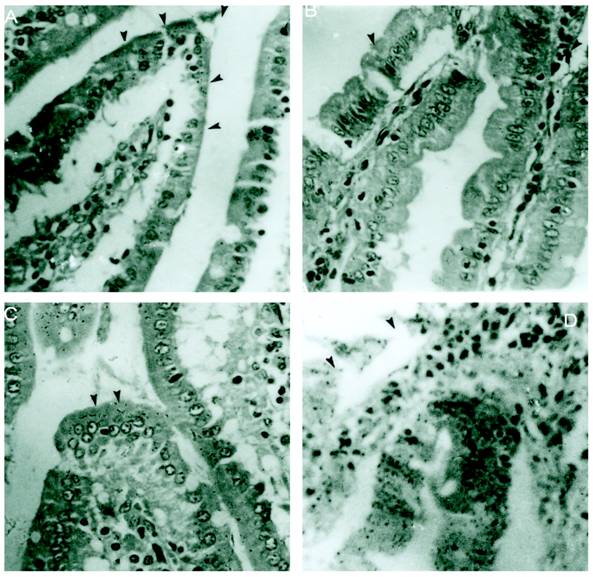

M cells present in the epithelium overlying PP are well known to be targeted by different enteropathogens, thereby enabling their uptake into the intestinal mucosa. In addition, alternative routes of entry via M cells outside of PP via lamina propria dendritic cells or by direct invasion of absorptive enterocytes have been proposed. The host has different ways to overcome the infection. Reports have shown that Salmonella disturbs the epithelial layers to cause the systemic infection. Previously it was also reported that SLP covers the surface of intestinal epithelial cells and it is possible that they might have some immunological role during infection. In the present study we asked if SLP on the epithelial surface layer has protective role during infection. To address this question, we did the histology of intestine from all these different groups mentioned in material and methods. As shown in figure 1A the control group has normal morphology and almost no or very less infiltration of pro-inflammatory cells. On the other hand, infected group as shown in figure 1D has extensive increase in the inflammatory cells, increased neutrophils and villi tips exhibited necrosis in the cross section. However the cross section from fat fed induced SLP along with infection (experimental group) showed increased fat vacuoles, increased inflammatory cells and a sub epithelial edema similar to that found in the fat fed group (1B), but no necrosis as shown in figure 1C. The proinflammatory cells were far less than from infection group alone. We asked whether the difference is more prominent at higher resolution. We used same set of groups and analyzed them by electron microscopy. As shown in figure 2, the transmission electron microscopic studies shows microvillus damage in the cross section of the rat duodenum given infection alone (figure 2D) while the microvilli from the fat fed infected group showed the shortening and broadening of microvilli, but not any damage to the villi (2C). These results suggested the protective role of fat induced SLP during infection. From electron microscopic examination, it is clearly shown the disruption of the microvilli from the infected group, which is not the case when SLP induced diet along with infection was given to these rats suggesting an important role of fat induced SLP during infection.

Figure 1

Histological sections of small intestinal villi shows no necrosis from S.typhimurium infected together with SLP induced diet. (A) Cross section of the normal small intestinal villi showing normal villus height. Arrows points to the normal pointed villus. (B). Cross section of the fat fed rat small intestinal villi showing edema in the lamina propria and broadening of villi. Arrows points to a broadened villus. (C) Shows fat deposited in lamina propria of the cross section of fat fed with S.typhimurium infected rat. (D) Demonstrates increased infiltration of neutrophils and also shows villus necrosis (arrow). Magnification x 40.